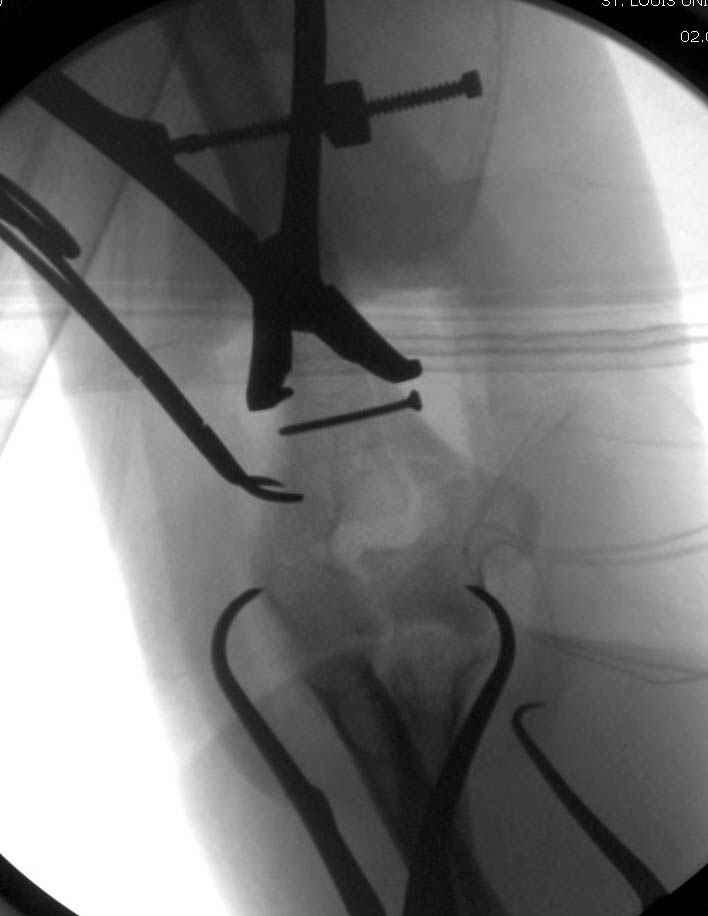

Djoldas Kuldjanov, M.D. 09 Сентябрь 2005, 20:07

Примерный случай, только перелом был открытый, в задне-медиальной стороне рана около 2 см по характеру "изнутри кнаружи", неврологический статус со слабостью сгибания мизинца, также слабая абдукция и аддукция указательного пальца и сгибания в кисти.

Больному сделали обработку и наложили временный аппарат внешной фиксации плечо-предплечье.

На шестой день сделали открытую репозицию чрезлоктевым доступом двумя locking plate, локтевой нерв был ушибленным, после операции положительная динамика в Flexor Carpi Ulnaris. Фиксацию локтевого отростка произвели tension band technique с дополнительным шурупом.

Этапы операции на снимках....